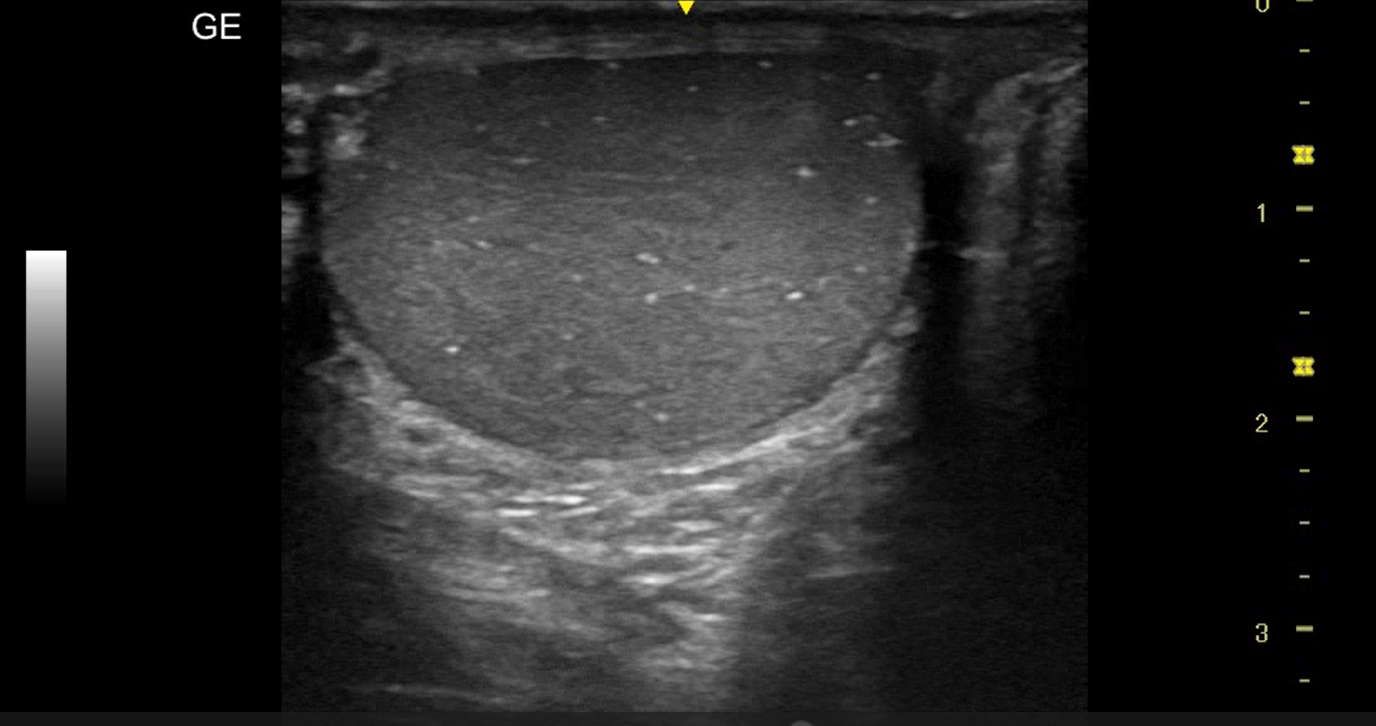

Realizamos ecografía clínica testicular: observamos ambos testículos con microlitiasis bilaterales puntiforme sin sombras acústicasen, en forma de cielo estrellado, vascularización normal, cabeza epidídimo izquierdo con leves signos inflamatorios, mínimo hidrocele.

La ecografía testicular reglada testicular realizada al mes presenta resolución de orquiepidimitis y confirma microlitiasis testiculares.

Microlitisis testicular bilateral en contexto de Orquiepidimitis aguda. Diagnóstico diferencial con tumor testicular, torsión testicular, absceso testicular, hidátide.